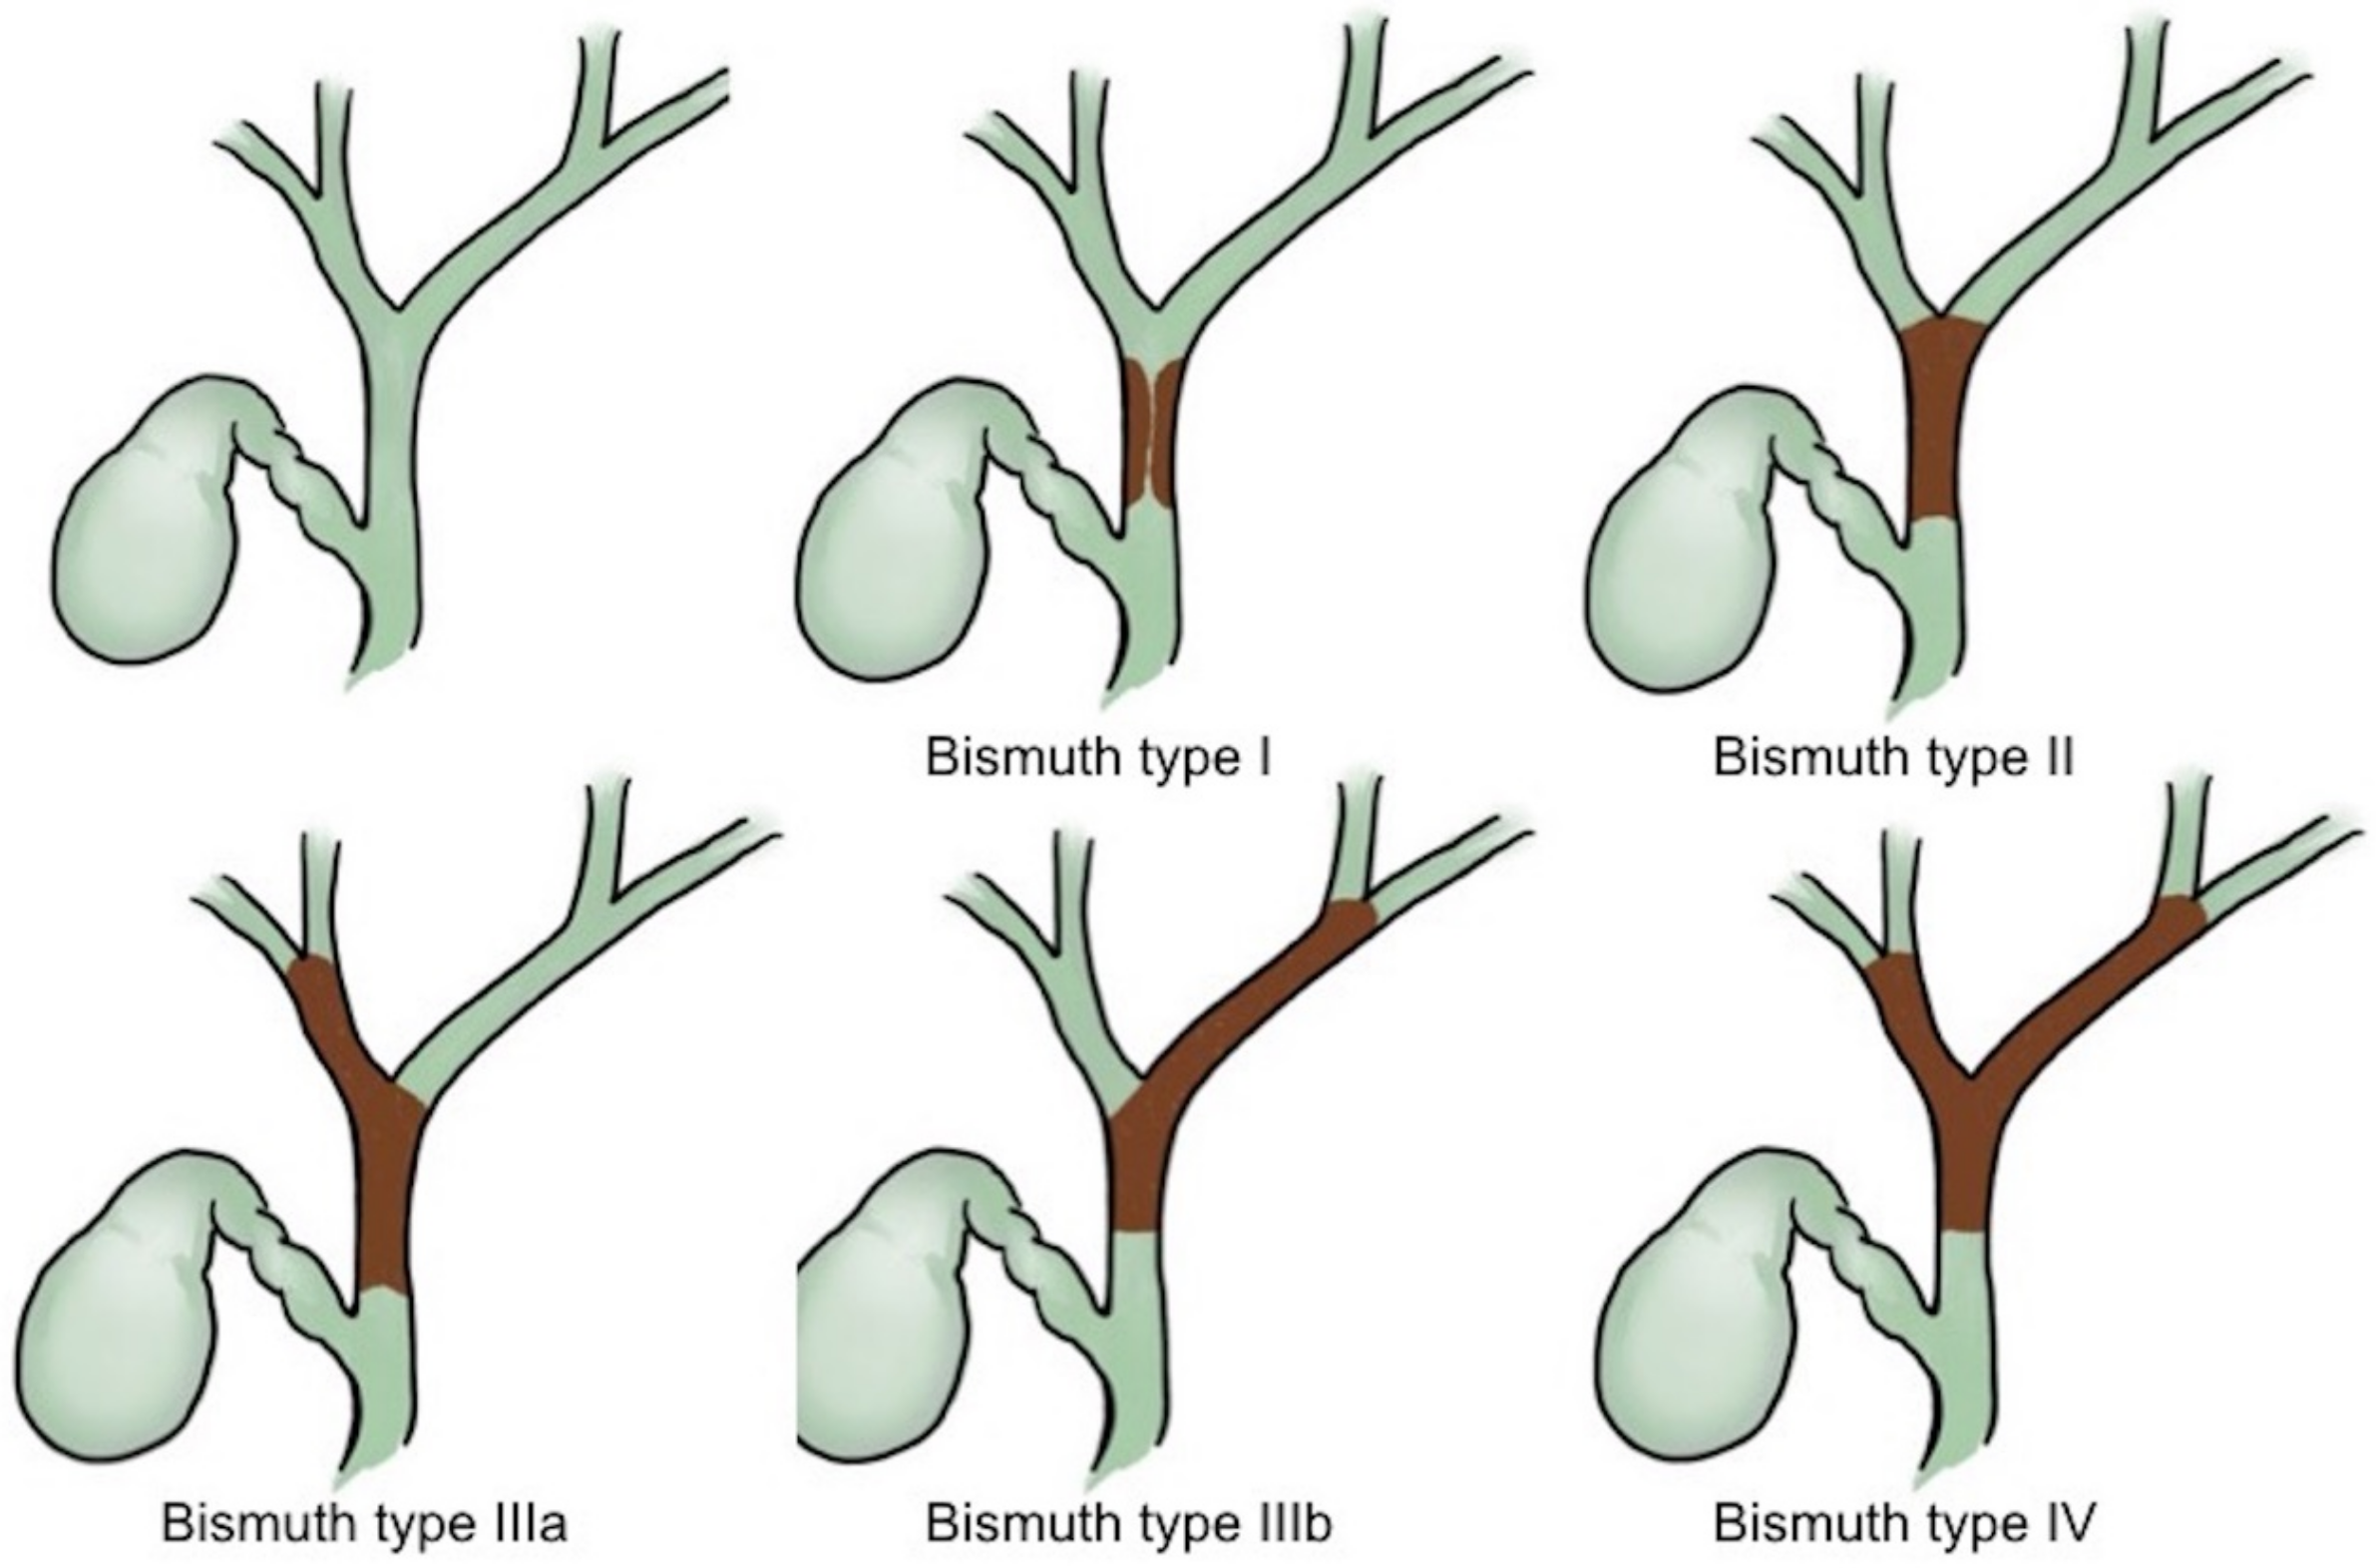

4. Malignant Hilar Biliary Obstruction

- Bismuth, H.; Nakache, R.; Diamond, T. Management strategies in resection for hilar cholangiocarcinoma. Ann. Surg. 1992, 215, 31–38. [Google Scholar] [CrossRef]

- Lee, S.H.; Park, J.K.; Yoon, W.J.; Lee, J.K.; Ryu, J.K.; Yoon, Y.B.; Kim, Y.T. Optimal biliary drainage for inoperable Klatskin’s tumor based on Bismuth type. World J. Gastroenterol. 2007, 13, 3948–3955. [Google Scholar] [CrossRef] [PubMed]

- Bismuth, H. Surgical anatomy and anatomical surgery of the liver. World J. Surg. 1982, 6, 3–9. [Google Scholar] [CrossRef] [PubMed]